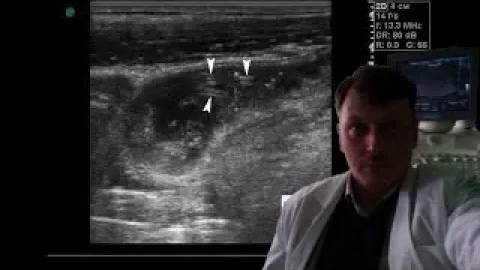

УЗИ щитовидной железы - Большой кистозно-солидный узел щитовидной железы смотреть онлайн

УЗИ щитовидной железы - Большой кистозно-солидный узел щитовидной железы